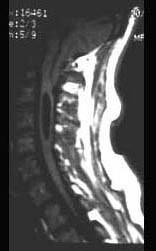

问题 该头颅MRI摄片提示 ( )

选项 A、寰枕融合 B、无脑畸形 C、扁平颅底 D、Arnold-Chiari畸形 E、小脑扁桃体肿瘤 一、单项选择题

答案 D